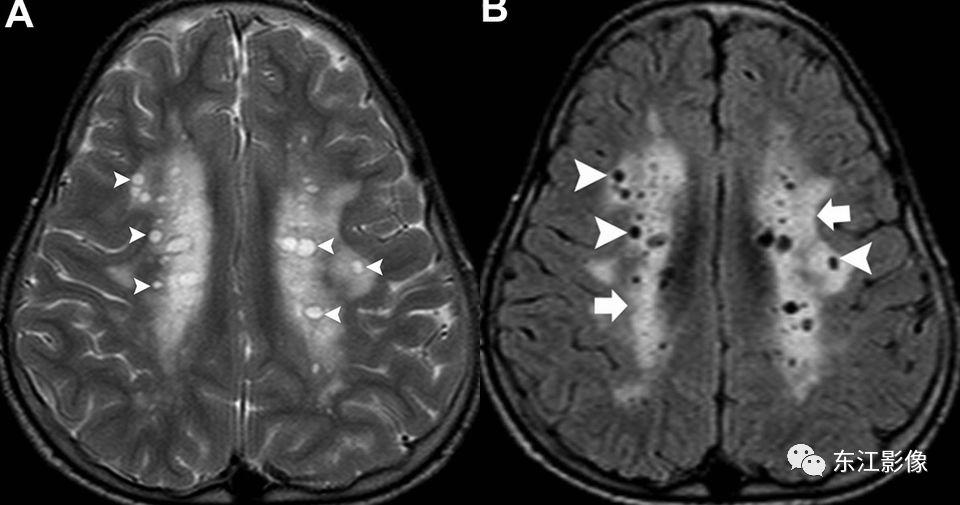

伴血管周围间隙扩大的其他疾病,如隐球菌感染,粘多糖病等

- 神经系统隐球菌感染常见于基底节区,“扩大的血管周围间隙”信号并非纯粹脑脊液样信号,邻近脑实质亦会信号异常;增强可强化。

- 粘多糖病罕见,“扩大的血管周围间隙”常见于半卵圆中心,多伴有脑发育不良等征象。

粘多糖病。引自:Kanekar S, Devgun P. A Pattern Approach to Focal White Matter Hyperintensities on Magnetic Resonance Imaging.